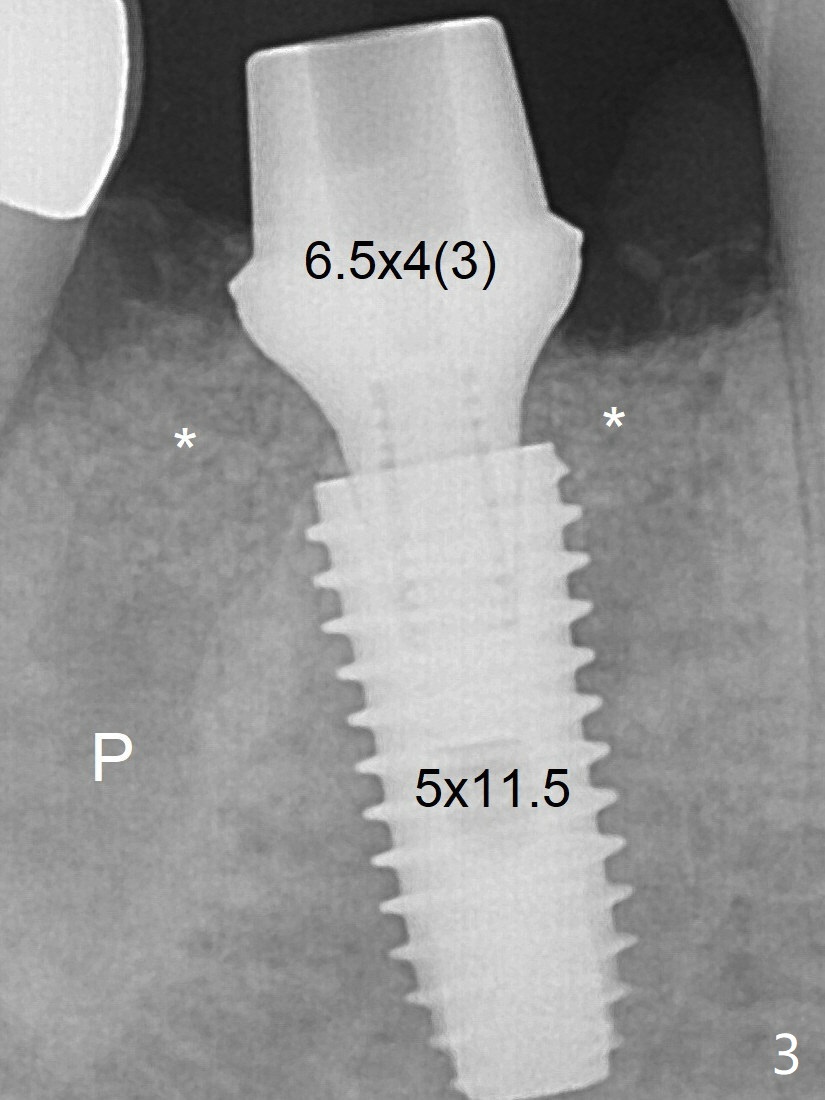

What is ignored is the mesial deviation of the initial osteotomy (Fig.2 <). The osteotomy shifts to the mesial socket with the next drill. The severity of the deviation is not found until a 5x11.5 mm implant is placed (Fig.3). While Osteogen plug is placed in the apical socket (P), Vanilla (allograft) mixed with Osteogen in the coronal socket (*). Because of tight schedule and partial flap (to remove fractured roots), periodontal dressing is applied around the immediately placed abutment (for retention). An angled abutment may be required before final impression because of the deviated implant. The implant seems to have osteointegrated 3.5 months postop (Fig.6, a month post abutment dislodgement).